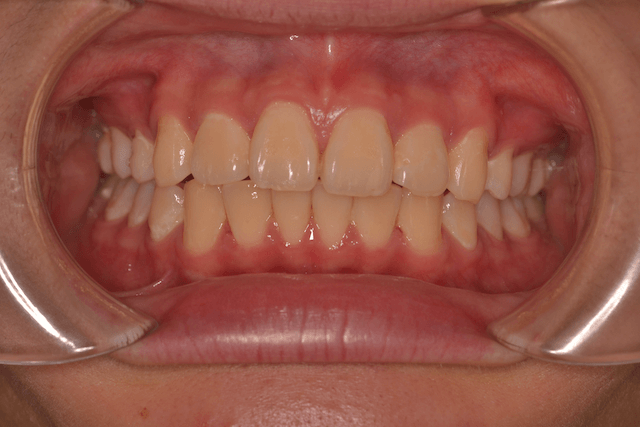

過蓋咬合を抜歯とDBSで改善した症例

※DBSとはダイレクトボンディングシステムと呼ばれており、ブラケットにワイヤーを通して歯を動かしていく矯正治療です。

患者情報

16歳女性

主訴

前歯がでてる

行った治療内容

上顎両側4番抜歯、DBS

治療のリスク

歯根吸収、前歯部歯肉退縮

治療期間

動的治療期間4年0か月

※ クリックして拡大することができます。